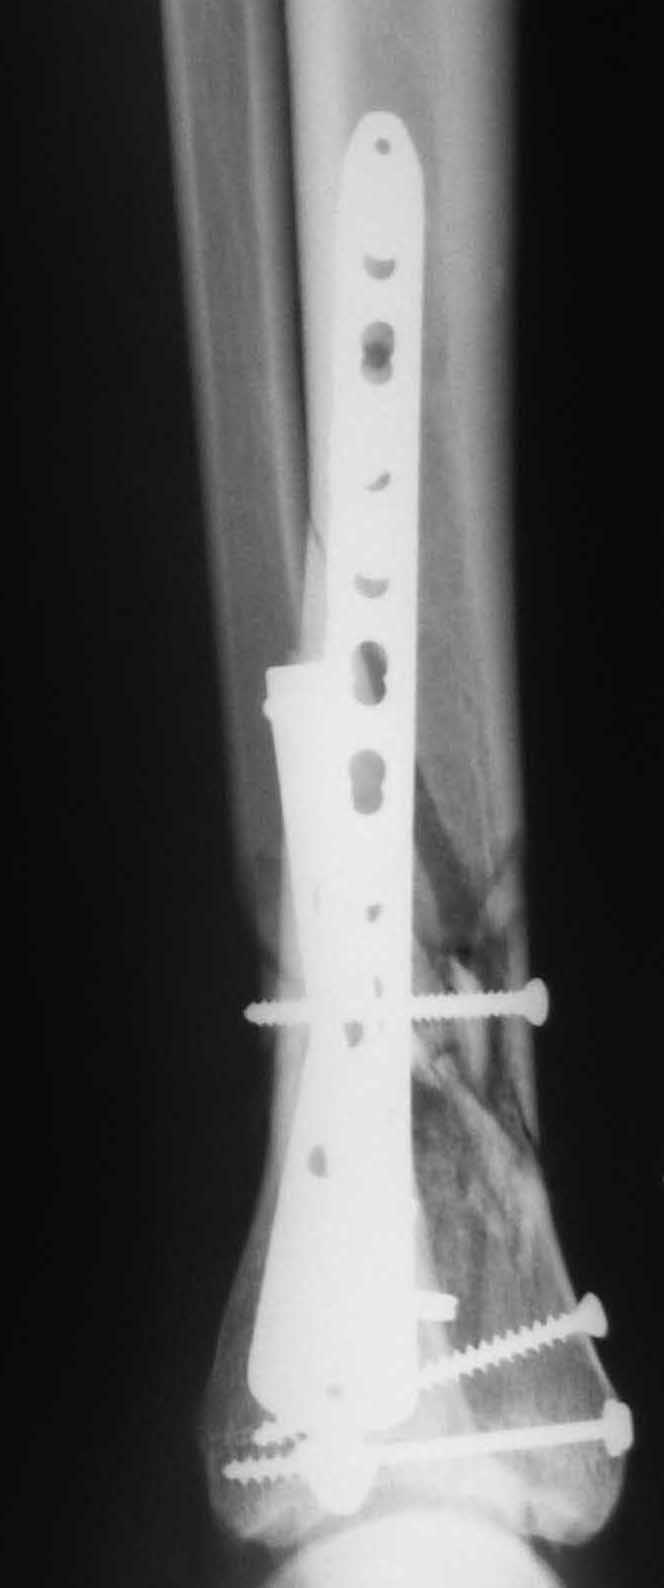

OK, Dr Driagin, Ja operiroval bolnogo po Vashemu, hotia sam ni ochen' ubezden' v itom, t.k. bolnoi otkazalsa na proch' ot ex.fix, ja emu sdelal ORIF + Kostnia plastika, snimky prelogiottsa,

Очень прилично получилось, но мне показалось, что винты на 4,5 мм.Это принципиально винты используются 3,5 и 4,0 мм. И проекцию прямую бы переделать. С уважением Дрягин

На представленном снимке видно, что эпифиз смещен латерально.

Сейчас с этим ничего не сделать, похоже.